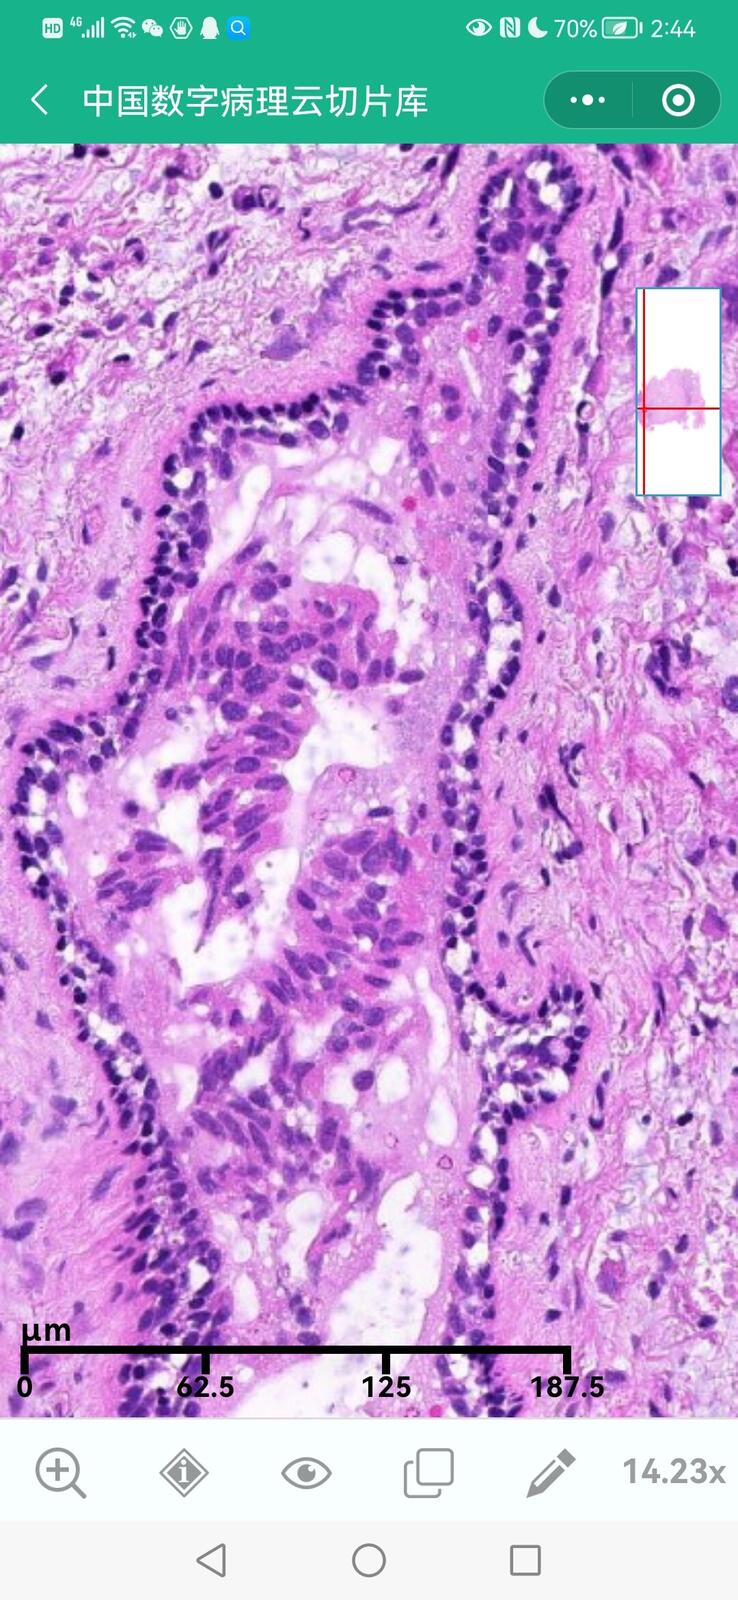

乳腺黏液性囊腺瘤伴导管内癌

乳腺多形性脂肪肉瘤

乳腺叶状囊肉瘤

乳腺分泌性癌(29岁)